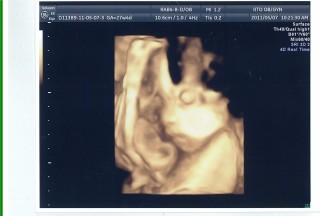

27w4d頭70.6㎜ お腹241.1㎜ 大腿骨51.7㎜ 体重1278.0g平均より1週大きめ。75gOGTT検査はクリアでき、ひと安心。(計7本も血液取るので案外と大変です。)逆子がなおり、前置胎盤も移動してきて、そしてなにより赤ちゃんが元気にすくすく育ってくれてます♪羊水過多ぎみで(^^;)胎動は感じにくいけど、それでもやっぱり主人の手のひらによく反応する赤ちゃんです。

大きめの1450gで先生にびっくりされました(笑) 臍の緒を枕にしている様でした☆